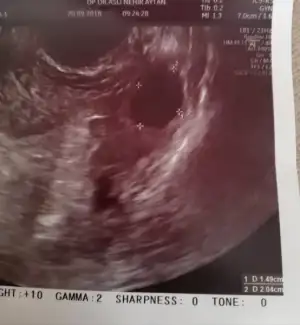

whiterabbit88 Kızlar Bn şimdi çıktım doktordan eve geldim çok şükür rabbim e yumurtacıklarıma birsey olmamış ikiside daha da büyüdü bi günde eridim bittim sandım Ordada tutamadım kendimi doktor iğne için mi geldin dedi hadı yap gel konuşalım dedi yok dedim önce konuşalım odaya girmemle ağlamam bir oldu anlattım hemen baktı birsey yok sakin ol bak daha da büyümüşler Bn onları şimdi çatlatıcam dedi.. Bana senı çok iyi görmüştüm ve çokta umutluyum ne olur stresi Bı kenara koy ve mutlu olmaya bak... Senin mutlu iyi hissetmen bu ilaçlardan da daha etkili ve önemli unutma dedi... Doktor çok üzüldü Bnim halime iğneyi bile normalde acilde özel hastane ücret alır öyle yaparlar hemşireye rica edip arayıp getirdi hemsirede hamileydi inş uğur getirir dedi..